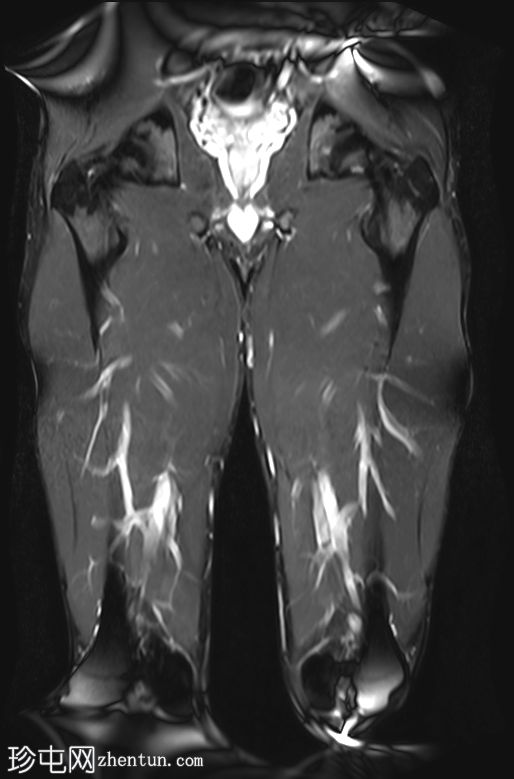

冠状位

T1 tirm

收肌长肌腱从耻骨起点完全撕脱,可见充满液体的间隙(4毫米),肌腱近端回缩。

相关的肌内水肿累及收肌长肌、短肌和耻骨肌,筋膜间液沿股薄肌向内侧延伸。

MRI 表现与收肌长肌腱从起点撕脱并远端回缩相符,可见充满液体的间隙、筋膜间液和肌肉拉伤。

根据英国田径协会肌肉损伤分类(BAMIC),该损伤被归类为 4c 级。